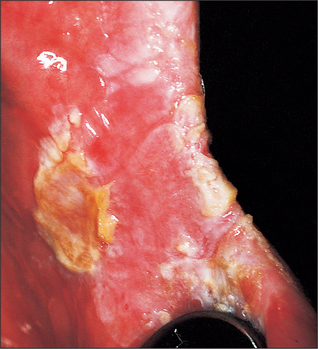

Sideropenic dysphagia (Plummer-Vinson syndrome, Paterson-Kelly syndrome) (Fig. 10.5)

In 1936 Ahlbom showed the relation between sideropenic dysphagia and oral cancer (Langdon and Henk 1995). Sideropenic dysphagia is particularly common in Swedish women, and accounts for the high incidence of cancer of the upper alimentary tract in this group and the higher incidence of women with oral cancer in Sweden. Of women with oral cancer in Sweden, 25% were sideropenic. The pathogenesis of oral cancer in such patients may be similar to that of syphilitic glossitis. The sideropenic dysphagia leads to atrophic epithelium, which is particularly vulnerable to carcinogenic irritants. Although the anaemia will respond to treatment with iron supplements, it is not known whether such treatment reduces the risk of subsequent malignant change.

image

Fig. 10.5 Severe mucosal atrophy in a patient with sideropenic dysphagia.